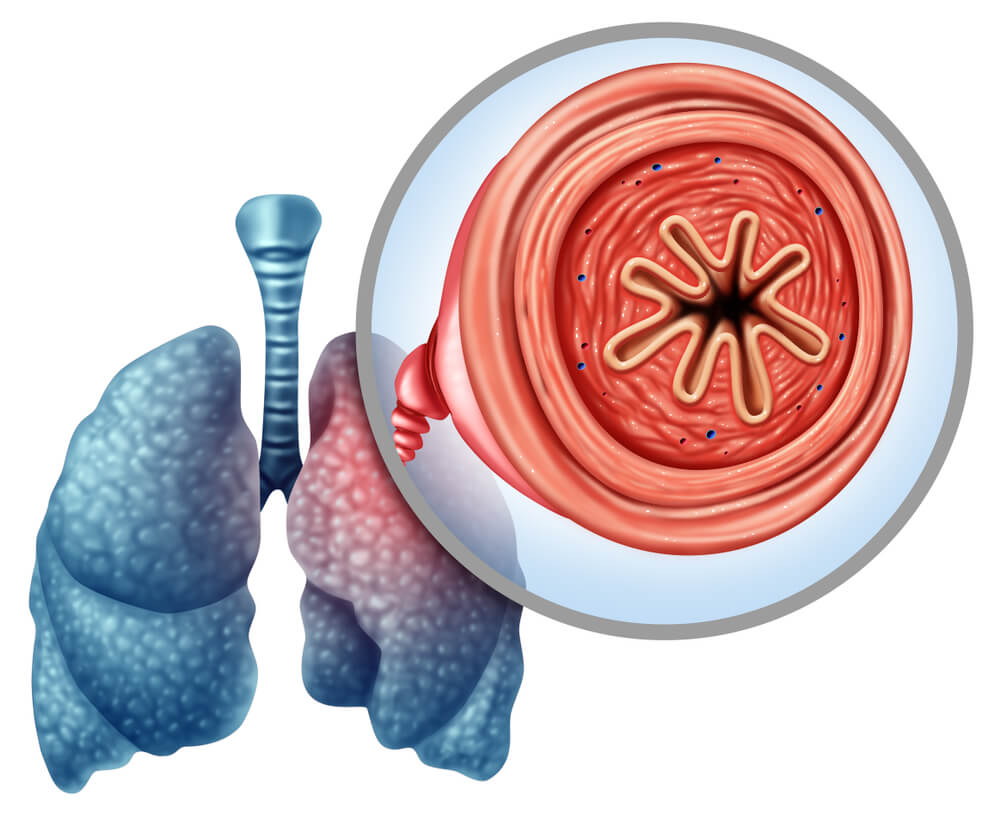

Para entender la EPOC es importante entender cómo funcionan los pulmones. En este sentido, el aire que respiramos baja por la tráquea a unos tubos que van a hacia los pulmones; son los tubos bronquiales o vías respiratorias.

Dentro de los pulmones, los tubos bronquiales se ramifican muchas veces en miles de tubos más pequeños conocidos como bronquíolos. A su vez, estas estructuras se siguen ramificando en racimos de diminutos sacos de aire redondeados denominados alvéolos.

En la EPOC, la cantidad de aire que entra y sale por las vías respiratorias disminuye. Algunas razones que justifiquen este hecho son:

- Los bronquios y los alvéolos pierden elasticidad.

- Las paredes que separan muchos de los alvéolos están destruidas.

- Los bronquios producen mucho moco y se pueden obstruir.

- Las paredes de los bronquios se engruesan y se inflaman.

- Bronquitis crónica: en este caso, los bronquios se inflaman y se estrechan, y los pulmones producen más mucosidad. De este modo, los bronquios se estrechan más y el grado de bloqueo aumenta.